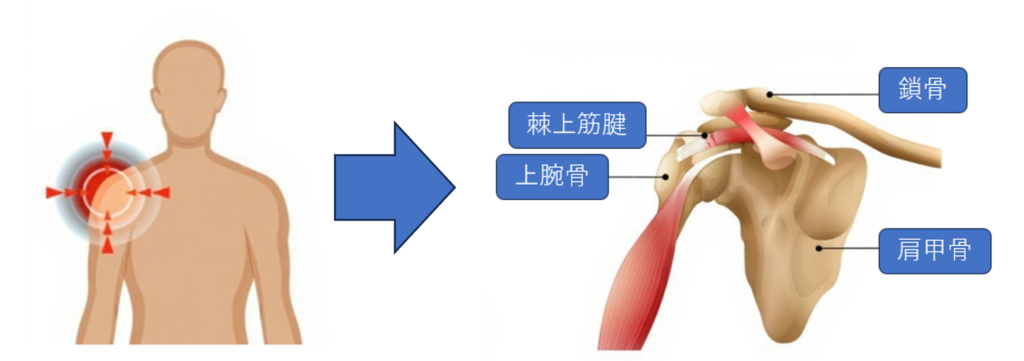

今回は棘上筋腱損傷の症例ついてご紹介します。

■棘上筋腱損傷

■棘上筋腱損傷

棘上筋腱は肩の腱板の1つで肩の腱板損傷で最も多い部位です。50代の男性で4人に1人が発症し、加齢と共に増加傾向にあるとの報告があります。

症例画像から図1~図4は棘上筋腱の画像です。□内に棘上筋腱の損傷を示します。正常では靱帯や腱は黒く描出されますが、損傷では白く高信号に描出されます。棘上筋腱損傷は、加齢による変性や転倒・スポーツ・仕事などによる外傷が原因となります。

症例画像から図1~図4は棘上筋腱の画像です。□内に棘上筋腱の損傷を示します。正常では靱帯や腱は黒く描出されますが、損傷では白く高信号に描出されます。棘上筋腱損傷は、加齢による変性や転倒・スポーツ・仕事などによる外傷が原因となります。